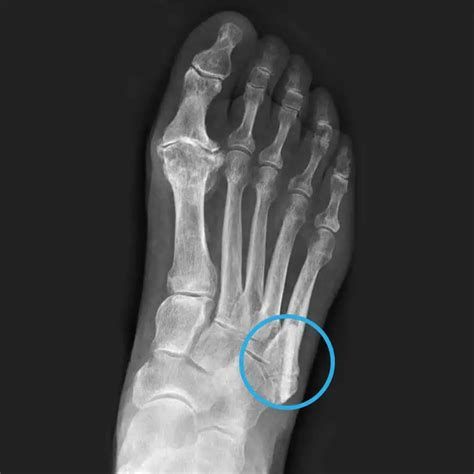

발 골절 수술 평균 비용은 얼마나 되나요

2025년 기준 발 골절 수술의 평균 비용은 약 1,650,000원입니다. 실제 사례를 보면 다음과 같은 범위를 보입니다:

- 최저 비용: 730,000원

- 최고 비용: 4,100,000원

- 평균 입원일수: 10.8일

이 수치는 발목을 제외한 발 골절(발등, 발가락 등)을 대상으로 전국 473개 의료기관(병원, 종합병원, 상급종합병원) 자료를 바탕으로 산출된 것으로, 건강보험이 적용된 기준입니다.

병원 규모, 골절 부위와 정도, 수술 방법, 비급여(특수 재료, 1인실 등) 유무, 입원 기간 등에 따라 비용은 큰 차이가 있을 수 있으므로, 실제 진료 전에는 해당 병원에 문의하여 정확한 견적을 확인하는 것이 안전합니다.

특히 발가락 등 비교적 단순한 골절 및 핀 제거, 짧은 입원만 필요한 경우에는 이보다 저렴하게(수십~수백만 원선) 나올 수도 있습니다